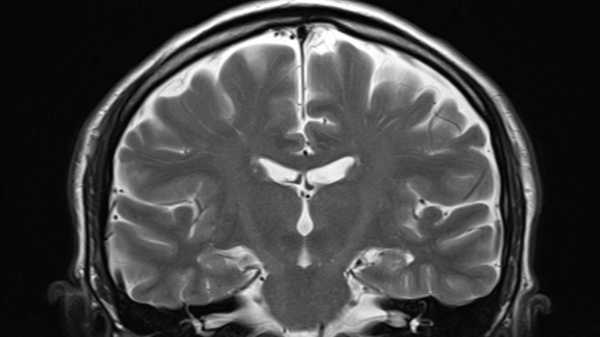

Ілюстрація, що показує пошкодження нейронів, яке може завдати розсіяний склероз. (Зображення: JUAN GAERTNER/SCIENCE PHOTO LIBRARY via Getty Images)

Розсіяний склероз (РС) – це аутоімунне захворювання, яке викликає запалення в головному та спинному мозку. Це запалення пошкоджує мієлінові оболонки – ізоляцію, яка огортає довгі «дроти» нервових клітин – і призводить до таких симптомів, як біль, втома, оніміння або слабкість, а також проблеми із зором або рухом.